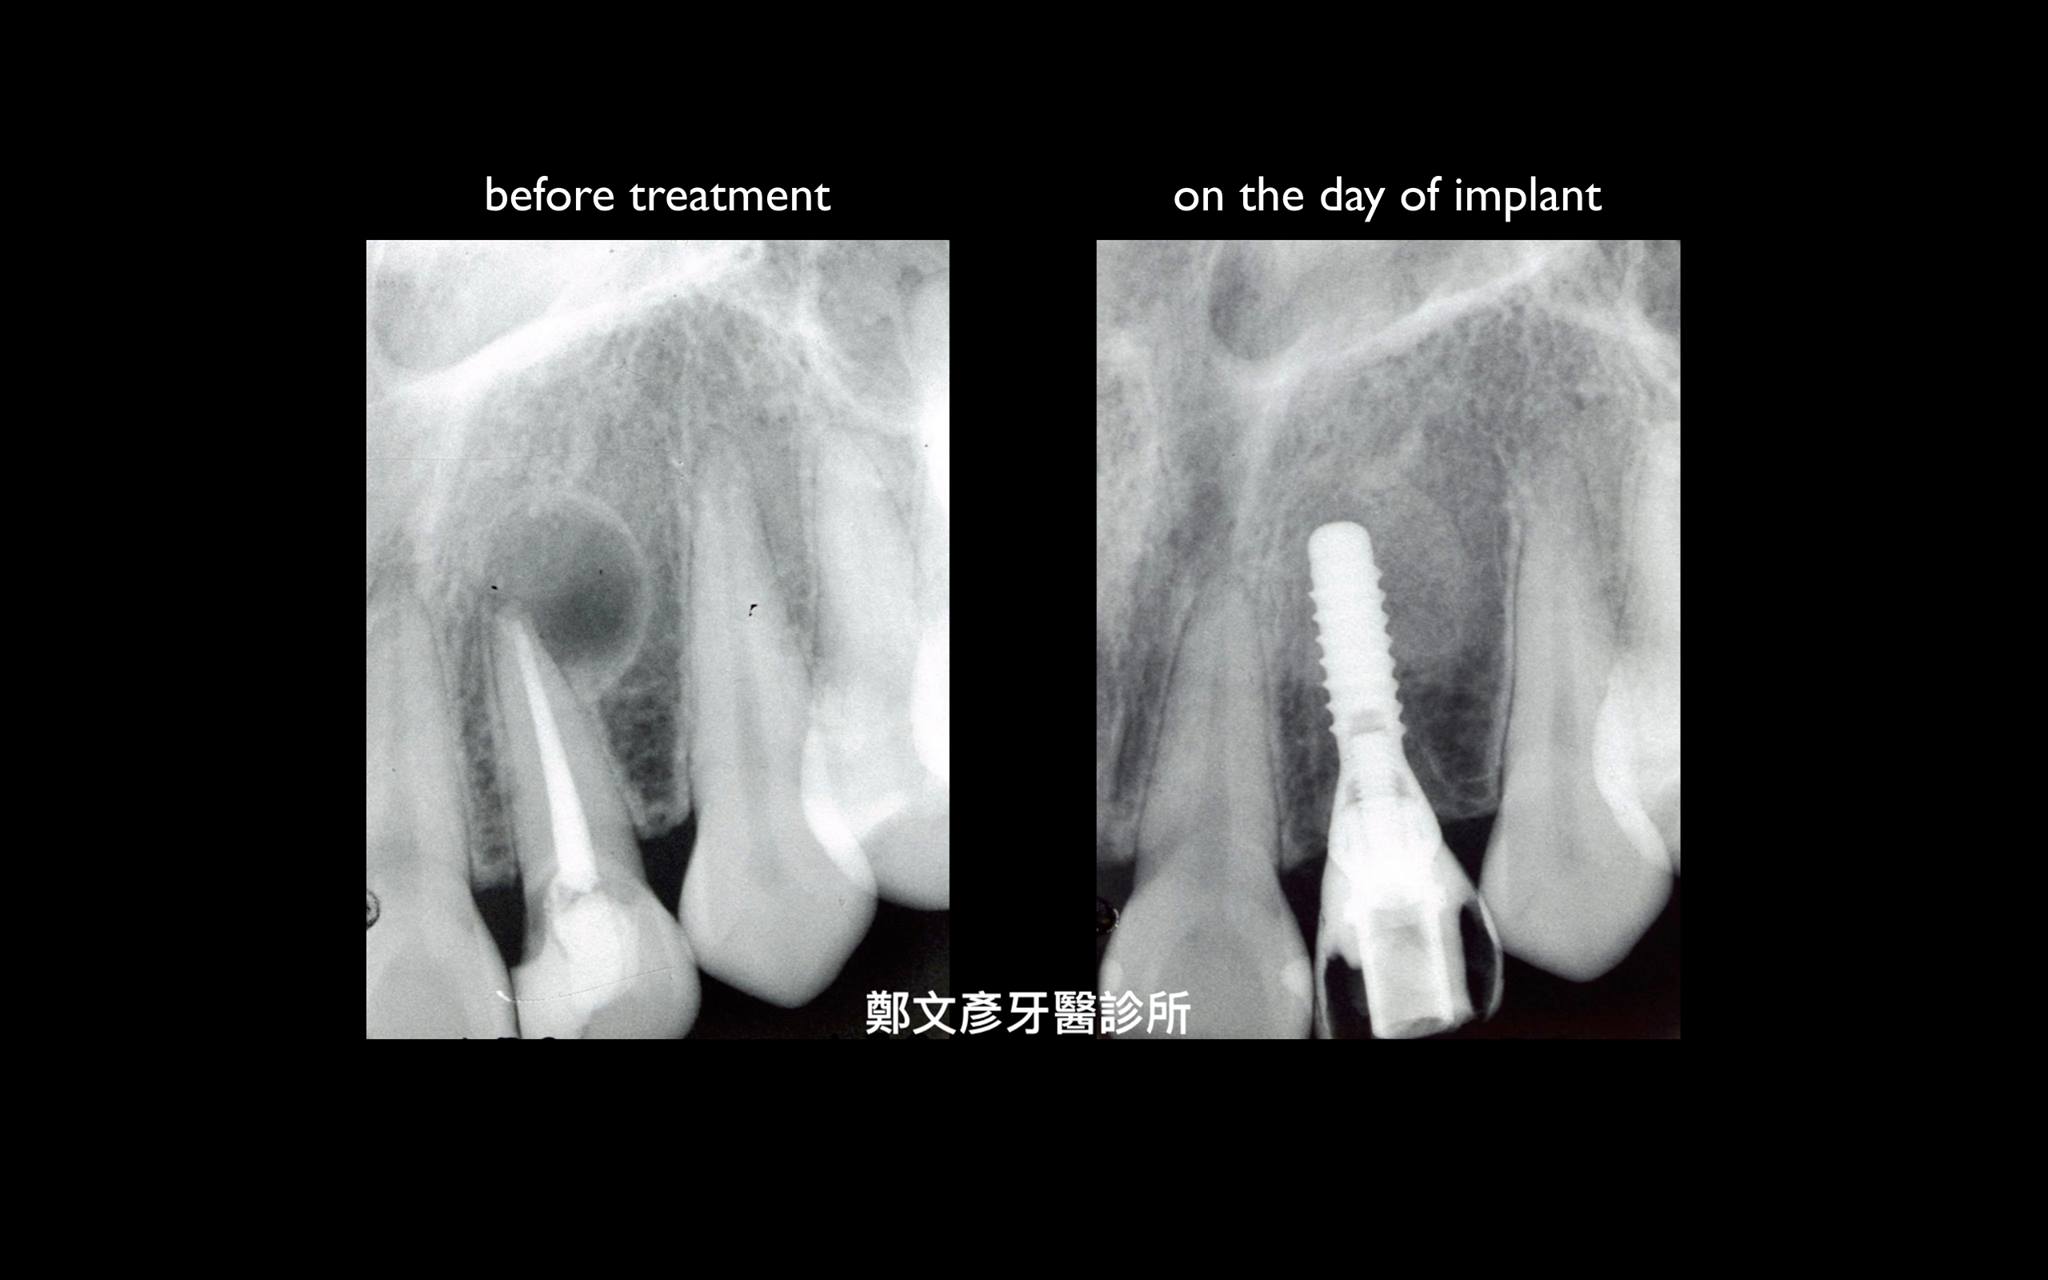

前牙植牙美學及軟組織轉移

植牙美學